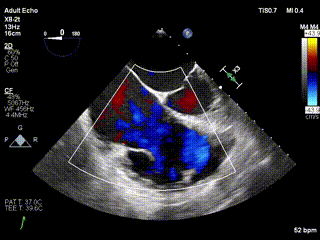

三例患者入院后,葛均波院士團(tuán)隊(duì)周達(dá)新教授、潘文志教授、張?jiān)床┦?、陳莎莎博士及心超室的潘翠珍教授、李偉教?/strong>對(duì)患者的情況進(jìn)行詳細(xì)評(píng)估和討論,最終決定為三例患者選擇LuX-Valve Plus40mm、50mm和50mm型號(hào)的瓣膜進(jìn)行手術(shù)治療。手術(shù)后即刻拔除氣管插管,術(shù)后患者三尖瓣反流癥狀得到顯著改善,復(fù)查心超結(jié)果顯示人工三尖瓣瓣膜支架固定穩(wěn)定,瓣葉關(guān)閉形態(tài)未見(jiàn)異常,未見(jiàn)明顯反流。